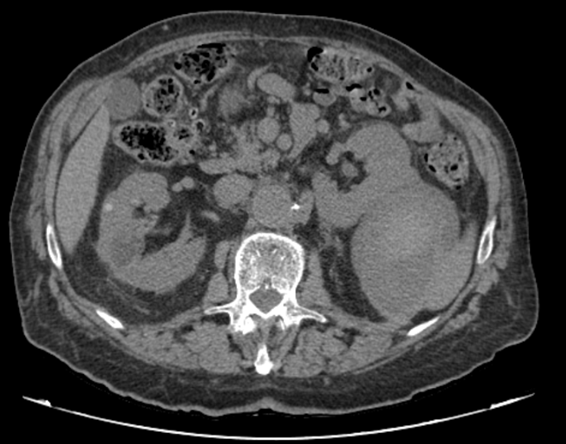

En el ámbito hospitalario se completa la evaluación con TAC abdominopélvico con contraste, que confirma la existencia de una gran lesión pararrenal izquierda de morfología quística, heterogénea y con contenido hemático, compatible con quiste renal hemorrágico. Se observan otros quistes simples y hemorrágicos en ambos riñones. La analítica realizada hospitalariamente no muestra cambios relevantes respecto a la de Atención Primaria y las endoscopias son normales.